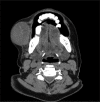

Salivary gland swellings can result from tumors, an inflammatory process or cysts. It can sometimes be difficult to establish; whether pathology arises from the salivary gland itself or adjacent structures. Neoplasms of the salivary glands account for less than 1% of all tumors, 3-5% of all head and neck tumors and benign pleomorphic adenoma (PA) of minor salivary glands arising de novo is very rare. PA is the most common tumor of the salivary gland. While the majority arises from the parotid gland, only a small percentage arises from the buccal minor salivary gland. A case of PA of minor salivary glands in the buccal mucosa in a 70-year-old female is discussed. It includes review of literature, clinical features, histopathology, radiological findings and treatment of the tumor; with emphasis on diagnosis.